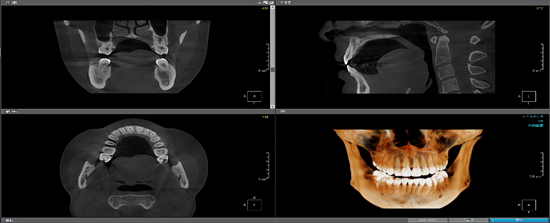

工作室团队成员目前包括李思博士、何远清老师、胡晨恺医生(南昌大学第二附属医院心内科主治医师)。另现有7名学生成员,包括20级1名、21级1名、22级5名,学生成员目前的研究主题包括:基于深度学习的冠脉造影狭窄智能检测技术研究(如图1所示);基于神经网络的智慧城市停车位检测技术研究(如图2所示);基于深度学习的口腔CT牙槽骨分割技术研究等(如图3所示)。

图1:基于深度学习的冠脉造影狭窄智能检测技术研究